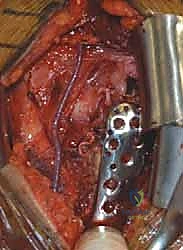

عندما تكون الكسور معقدة، نازحة بشدة، أو متعددة الأجزاء، يصبح التدخل الجراحي أمراً حتمياً لضمان شفاء العظم في وضعه التشريحي الصحيح واستعادة حركة الكتف. يقدم الأستاذ الدكتور محمد هطيف أحدث الخيارات الجراحية العالمية في صنعاء:

1. الرد المفتوح والتثبيت الداخلي (ORIF - Open Reduction and Internal Fixation)

هذا هو المعيار الذهبي لعلاج معظم الكسور النازحة (جزأين أو ثلاثة أجزاء، وبعض كسور الأربعة أجزاء لدى الشباب). يقوم الدكتور هطيف بفتح الكتف، وإعادة ترتيب الشظايا العظمية بدقة متناهية (الرد المفتوح)، ثم تثبيتها باستخدام شرائح معدنية تشريحية ذاتية القفل (Locking Plates - PHILOS) ومسامير.

* ميزة الشرائح ذاتية القفل: تمنح تثبيتاً قوياً جداً حتى في العظام الضعيفة والمصابة بالهشاشة، مما يسمح للمريض ببدء العلاج الطبيعي في وقت مبكر.